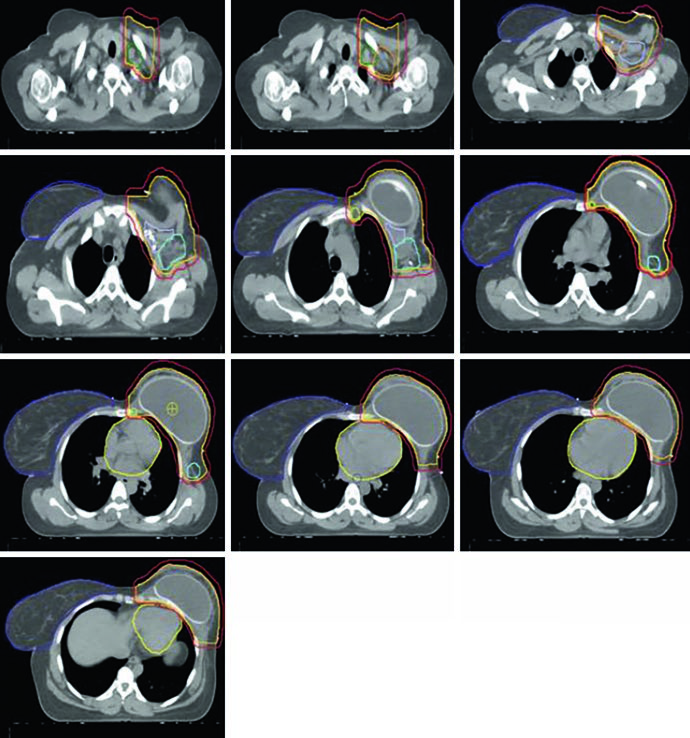

In the post-mastectomy setting without reconstruction, the chest wall constitutes the primary CTV alongside the nodal volumes. Figures 12.1 and 12.2 (coronal and sagittal) and Figure 12.3 (axial slices) illustrate how the contours are distributed: the PTV follows the curvature of the remaining chest wall, with nodal stations contoured contiguously.

Without a prosthesis or expander in the field, planning is more straightforward. The chest wall is relatively flat, allowing tangents with conventional angulation. The main challenge lies in ensuring uniform skin coverage and adequate retrosternal coverage where the IMN reside, without excessive ipsilateral lung dose. The absence of prosthetic volume reduces dosimetric complexity but does not eliminate the need for optimization — especially at the junction between tangential and supraclavicular fields.

Reconstructed (Tissue Expander) Left Chest Wall

When the patient has tissue expander reconstruction, the planning geometry changes significantly. The expander protrudes the chest wall anteriorly, altering target depths and the spatial relationship with OARs. On the left side, the heart assumes a relatively more anterior position, requiring careful optimization. Figure 12.4 clearly shows the cardiac contour (yellow) in relation to the PTV in the sagittal view — this proximity explains the laterality-specific dosimetric limits.

Figure 12.5 shows axial slices for the reconstructed left chest wall. Note how the PTV encompasses the expander bilaterally and how nodal stations maintain their standard contours despite the anatomical alteration. The prosthesis itself is included in the CTV — the IMRT/VMAT criteria specify that the $D_{95\%}$ inside the implant PTV should not exceed 120% of the prescription, an essential limit to avoid damage to the prosthetic material and capsular complications. In practice, hot spots above 120% over silicone or saline expanders can cause accelerated encapsulation and complicate subsequent reconstructive surgeries.